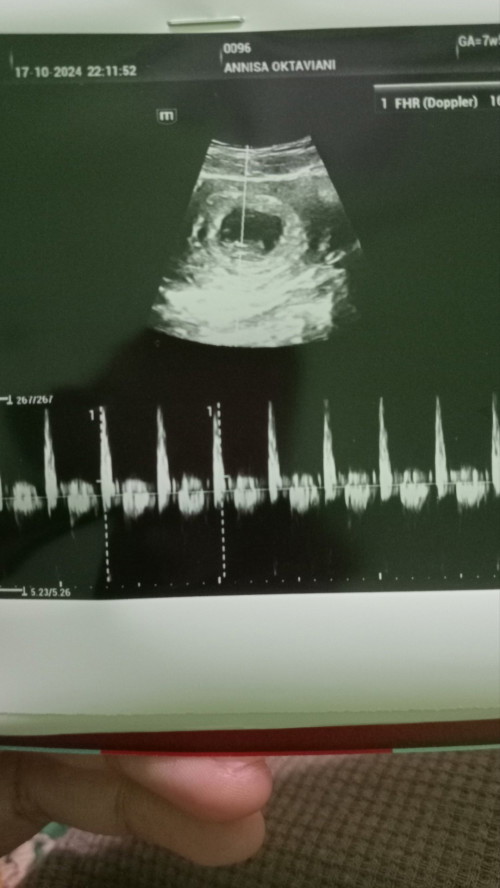

Baca lagiaku dulu juga kayak gitu bun, dari hamil 5 week sampai 12 week bun. pas di periksa usg wktu 5 week kan masi kantong. jdi di suruh balik 8 week lagi, pas 8 week baru nampak dimana penyebab flekny, karna kantong kehamilan itu belum melekat sepenuhnya ke rahim, ini sya liatkan usgnya bun,

Baca lagialhamdulilahnya janin gak kenapa2. sehat2 aja bun.